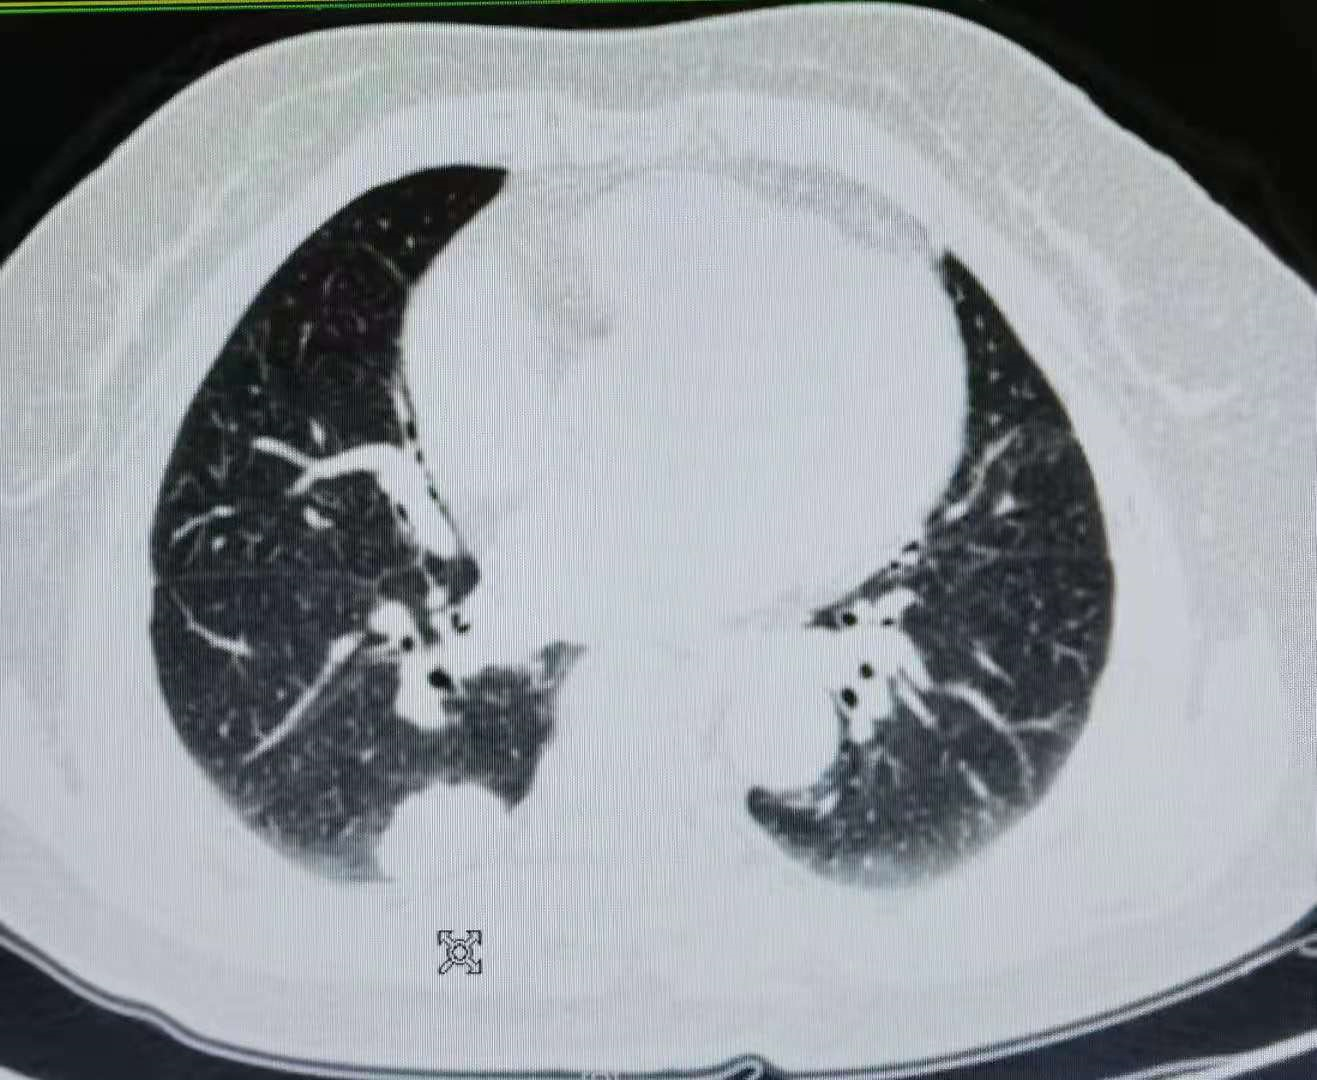

患者 , 孙某 , 女 , 66岁 , 患者2018年03月体检胸部CT:右肺下叶纵隔旁占位 , 约31mm*19mm 。 见图1、2、3 。 进一步行PET-CT检查 , 提示:右肺下叶后基底段大小约3cm*1.9cm的扁圆形软组织肿块 , FDG代谢异常增高 , 与胸膜宽基底相连 , 右胸廓入口、气管前腔静脉后、主动脉弓、右食管旁多发肿大淋巴结 , FDG代谢增高 , 考虑转移 。